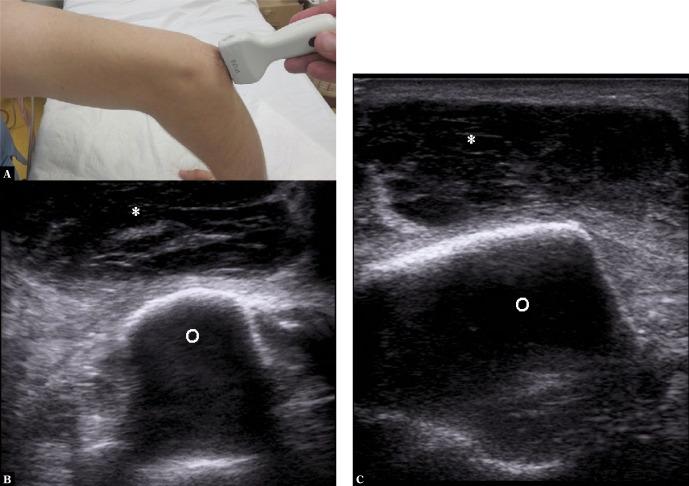

High-resolution ultrasonography has many advantages in the imaging of the musculoskeletal system, when compared to other imaging methods, particularly in superficial, easily accessible parts of the body. It is a perfect diagnostic tool for visualizing the most common pathologies of the musculoskeletal system, including the bursae. Inflammation of bursae is frequent, and it can mimic other diseases of the musculoskeletal system. Therefore, knowledge of normal ultrasound anatomy of the bursae, their exact location in the human body, and the sonographic signs of their most common pathologies is essential for establishing a quick and accurate diagnosis by ultrasound. Common conditions affecting bursae, leading to bursitis, include acute trauma, overuse syndromes, degenerative diseases, inflammatory conditions (rheumatoid arthritis, psoriatic arthritis, gout etc.), infections such as tuberculosis, synovial tumors and tumor-like conditions (pigmented villonodular synovitis, osteochondromatosis), and many more. This review article presents and explains ultrasound examples of the most frequent pathological conditions affecting bursae. Images include normal and pathological conditions of bursae around the shoulder joint, elbow, hip, knee, and ankle joint.

与其他成像方法相比,高分辨率超声在肌肉骨骼系统成像方面具有许多优势,尤其是在身体浅表、易于检查的部位。它是可视化肌肉骨骼系统最常见病变(包括滑囊)的理想诊断工具。滑囊炎很常见,且可能与肌肉骨骼系统的其他疾病相似。因此,了解滑囊的正常超声解剖结构、它们在人体中的准确位置以及其最常见病变的超声征象,对于通过超声快速准确地做出诊断至关重要。影响滑囊并导致滑囊炎的常见情况包括急性创伤、过度使用综合征、退行性疾病、炎症性疾病(类风湿性关节炎、银屑病关节炎、痛风等)、感染(如结核病)、滑膜肿瘤和肿瘤样病变(色素沉着绒毛结节性滑膜炎、骨软骨瘤病)等等。这篇综述文章展示并解释了影响滑囊的最常见病理状况的超声实例。图像包括肩关节、肘关节、髋关节、膝关节和踝关节周围滑囊的正常和病理状况。